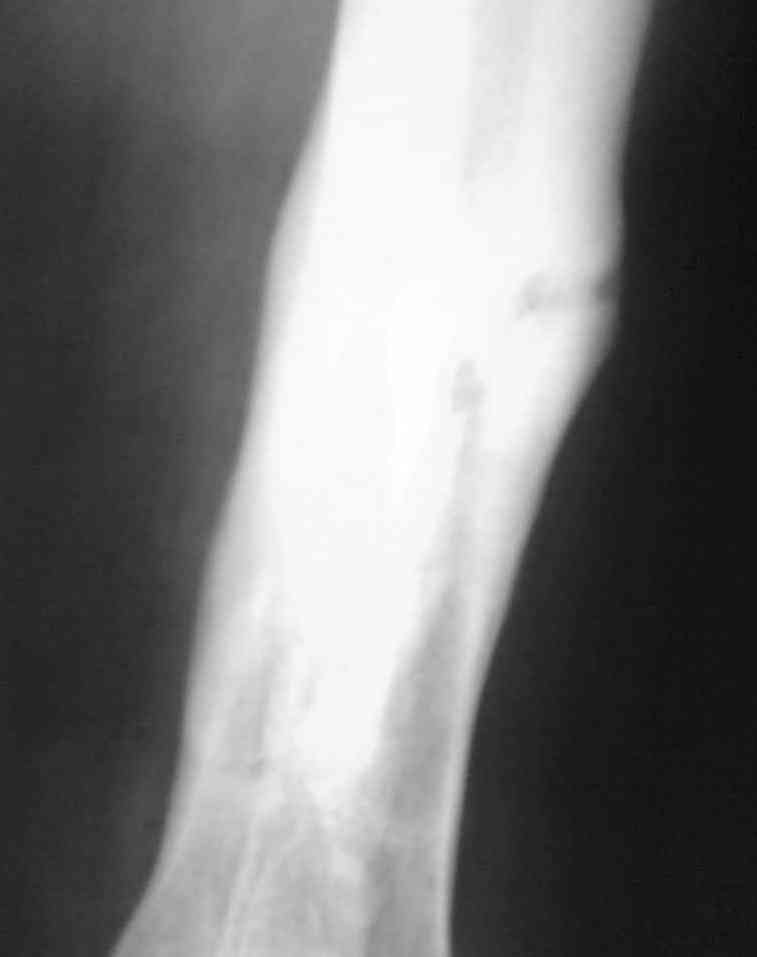

Выкладываю снимки в хронологическом порядке. Снмки все какие есть у больного.